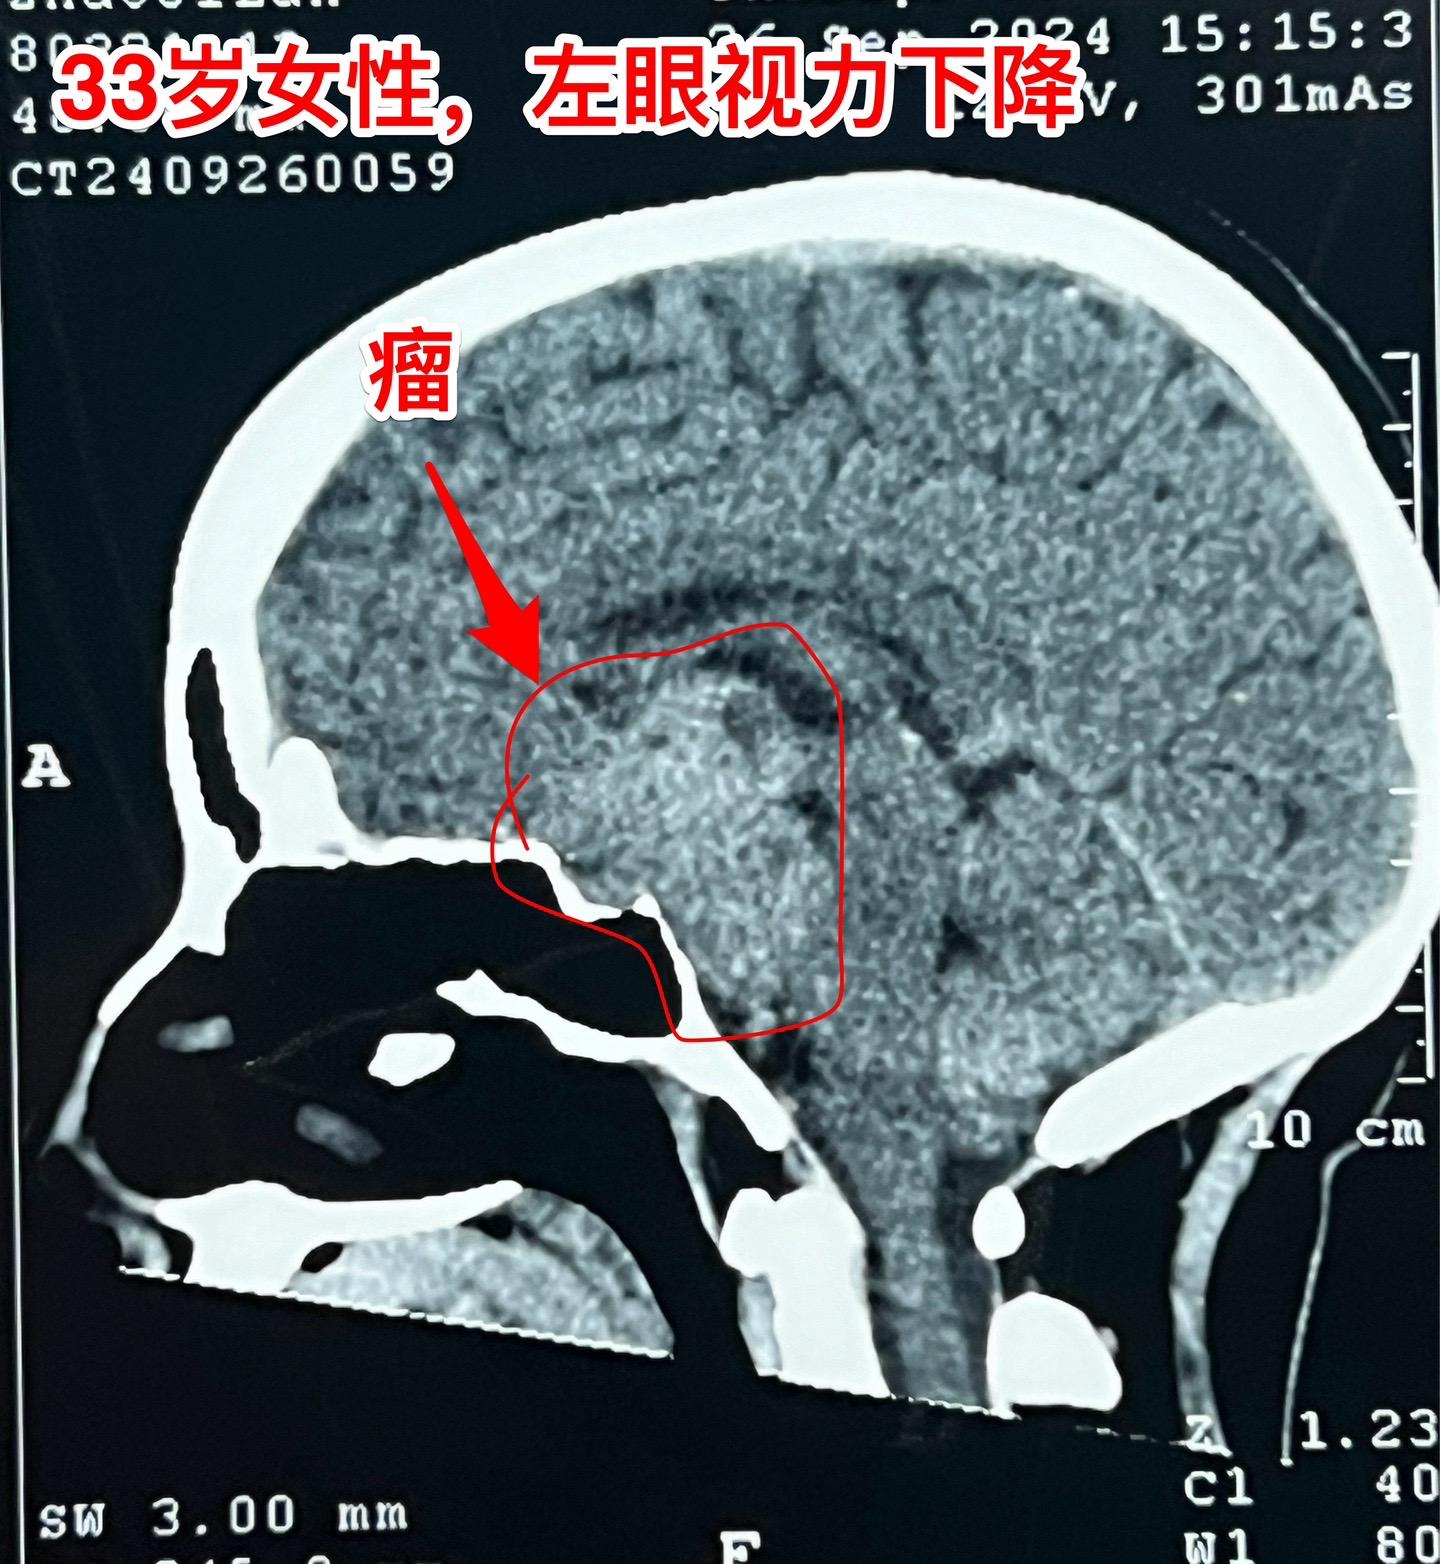

国庆节长假后第一天完成两个手术。一个手是33岁女性,来自云南省香格里拉。因左眼视力下降,到医院检查发现鞍区肿瘤,怀疑是颅咽管瘤。病人没有内分泌功能障碍。影像学上肿瘤是实性的,没有钙化,而且可以看见垂体信号。到底是什么肿瘤呢?今天手术中取肿瘤标本作快速冰冻病理检查,报告是垂体瘤。肿瘤得到完全切除,手术后病人视力好转了。 另一个手术是11岁男孩子,颅咽管瘤复发。经原切口翼点入路将肿瘤完全切除。术前磁共振只看见一个圆形肿瘤,术中发现除了这个肿瘤外还有5个散在的钙化斑,均得到完全切除。这样的散在钙化斑是潜在的危险因